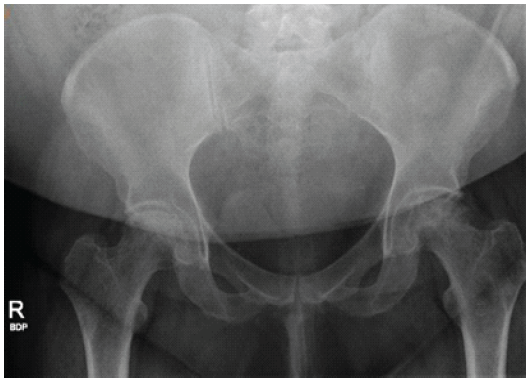

A 37-year-old woman with a body mass index (BMI) >40 presented to our orthopedic clinic in April 2024 for shoulder and hip pain. She was a non-smoker and denied drug and alcohol use. She reported first noticing joint pain in November 2023, approximately 2 years and 4 months after a severe COVID-19 infection in July 2021. Her COVID-19 disease process was complicated by asystole, acute kidney injury (AKI), shock liver, and acute encephalopathy. In the hospital, her AHRF was managed with intubation and a cumulative dose of 1640 mg of steroids. Before COVID-19, her past medical history included Class III obesity, prediabetes, polycystic ovarian syndrome, hypertriglyceridemia, hypertension, chronic bronchitis, anxiety, and depression. She was taking no chronic steroids; her bronchitis was managed with albuterol and montelukast. Initially, the patient’s COVID-19 infection was diagnosed at the pharmacy, but she later presented to the emergency department for respiratory distress, where 2 days of 20 mg of prednisone were prescribed. Due to worsening symptoms, the patient was then hospitalized for AHRF and received 40 mg of methylprednisolone twice per day. After succinylcholine administration for intubation, she went asystolic and needed cardiopulmonary resuscitation. After reanimation, transesophageal echocardiography showed a transient cardiomyopathy with reduced ejection fraction at 45–50%. Laboratory values showed elevated D-dimer levels, peaking at 17.73 mg/L (normal <0.5 mg/L), and elevated inflammatory markers, specifically an interleukin-6 of 56.54 pg/mL (normal <7.01 pg/mL), C-reactive protein of 279.30 mg/L (normal < 5 mg/L), and procalcitonin of 0.11 ng/mL (normal <0.1 ng/mL). During hospitalization, creatinine levels increased, indicating AKI; her alanine transaminase rose to 1318 U/L, indicating shock liver. She was also diagnosed with acute encephalopathy, evidenced by abrupt neurological changes, disorientation, reduced concentration, and slow speech. Overall, she spent 27 days in the hospital and received 1640 mg of steroids. After discharge, she received rehabilitative care at a nursing home. In November 2023, approximately 2 years and 4 months after being admitted for COVID-19, she was referred to rheumatology by her primary care physician for hip, knee, and shoulder joint pain of unknown etiology. With a history of metabolic encephalopathy overlying preexisting anxiety and depression, radiographic imaging without osseous findings, a positive antinuclear antibody, and no other rheumatological biomarkers, the rheumatologist diagnosed her with fibromyalgia. In March 2024, she was referred to a bariatric arthroplasty clinic for worsening hip pain and new-onset numbness and tingling. At the clinic visit, she had a positive Stinchfield test, and she reported a previous magnetic resonance imaging (MRI) of her left knee that had shown evidence for bone infarcts. Radiographic imaging of the hips was performed, showing bilateral AVN with collapse of the left femoral head. The patient was told that total joint arthroplasty was not an option at that time due to her elevated BMI and inflammatory markers. In April 2024, her primary care physician referred her to our orthopedic clinic for joint aspiration and intra-articular steroid injections. At that time, she was barely able to walk and also complained of increasing shoulder pain. Physical examination showed bilateral pain on palpation over the greater trochanters and the biceps tendons; she had a positive apprehension test and reduced shoulder range of motion. In April 2024, bilateral hip fluid aspiration with intra-articular steroid injections was performed. No marked effusions were found, and fluid cultures failed to show growth. Pain relief from the steroid injection lasted 2 weeks. Being a poor surgical candidate, in June 2024, bilateral femoral head core decompressive surgery was performed to try to delay total hip arthroplasty (THA) by improving interosseous blood flow. Due to continued pain, in August 2024, the shoulders and hips were imaged. Radiographs of the hips indicated no improvement of AVN despite decompressive surgery; there was Ficat-Arlet stage IV AVN bilaterally with crescentic sclerosis and bilateral femoral head collapse with greater collapse of the left femoral head (Fig. 1). Bilateral computed tomography angiography of the shoulders showed AVN affecting 75% of the surface areas in the humeral heads bilaterally, bilateral tendinosis of supraspinatus and infraspinatus muscles, and some degenerative changes in the long head of the right biceps (Fig. 2 and 3).

Figure 1: Radiograph of the pelvis of a 37-year-old woman with multifocal osteonecrosis. The image was obtained on August 21, 2024, approximately 2 weeks after core decompression and before total hip arthroplasty. The severity of avascular necrosis was diagnosed at Ficat and Arlet Stage IV bilaterally because of bilateral head collapse.